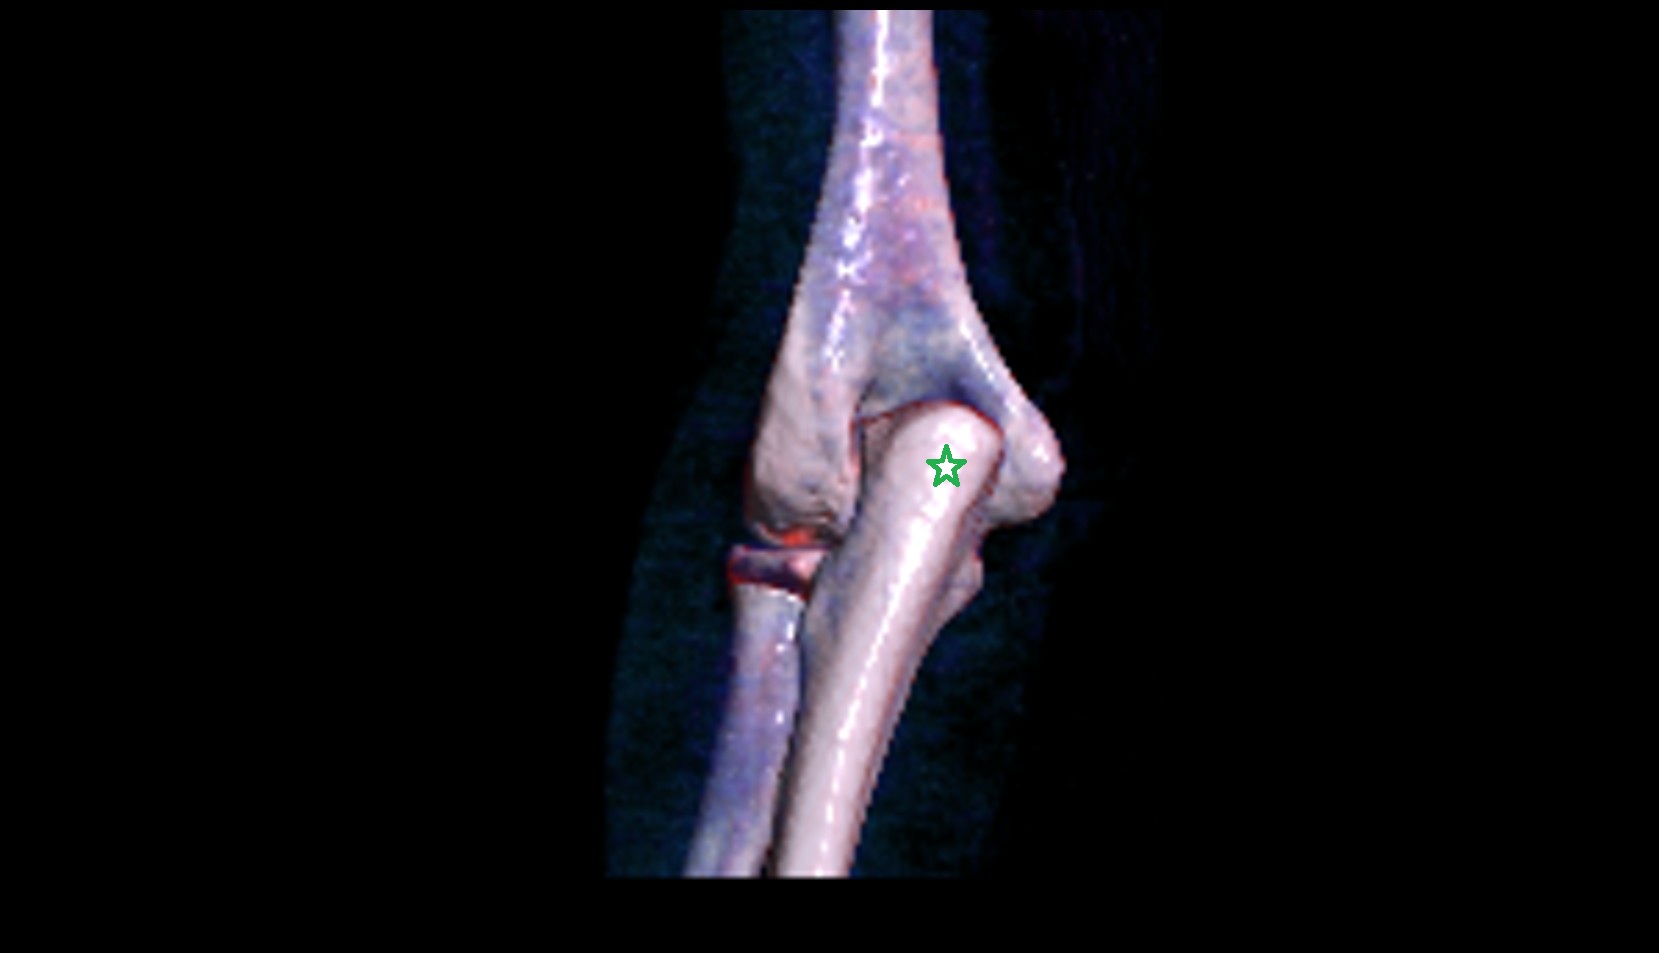

- Elbow joint

- Olecranon

- Coronoid process of ulna

- Capitulum of humerus

- Trochlea of humerus

- Head of radius

- Neck of radius

- Lateral epicondyle of humerus

- Medial epicondyle of humerus

- Lateral collateral ligament complex of elbow

- Medial collateral ligament complex of elbow (ulnar collateral ligament)